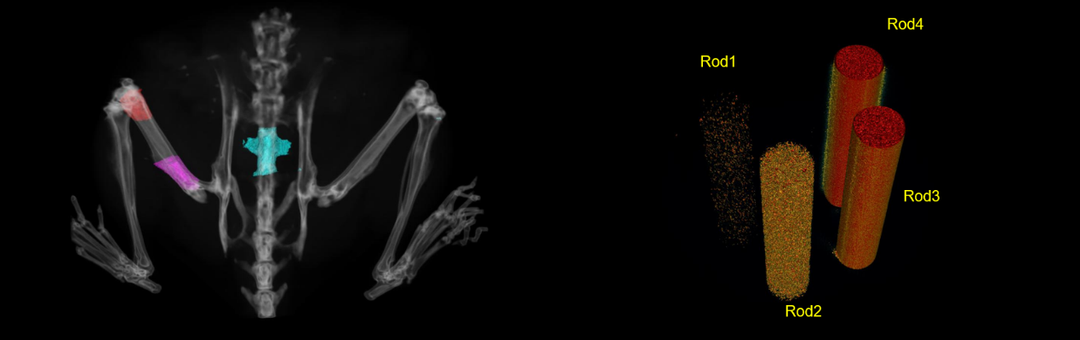

活体下,测定骨密度支持自定义区域以及长度,如红色区域股骨远端,紫色区域股骨近端及脊椎骨等。Rod1、Rod2、Rod3、Rod4分别为不同密度的羟基磷灰石。